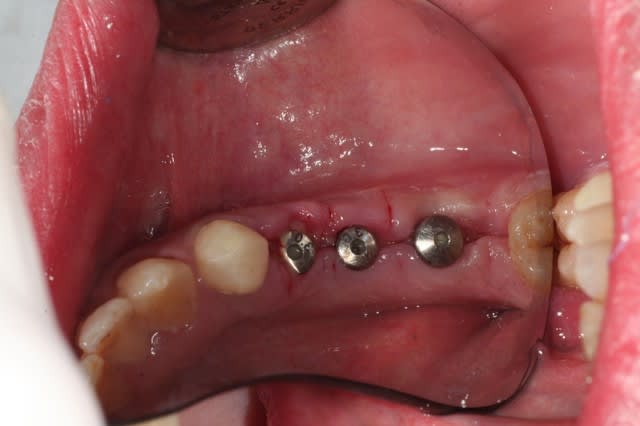

ce matin, pose de trois implants.

salut les petits clous...

voilà, je me suis remis un peu au boulot.

voici quelques images....